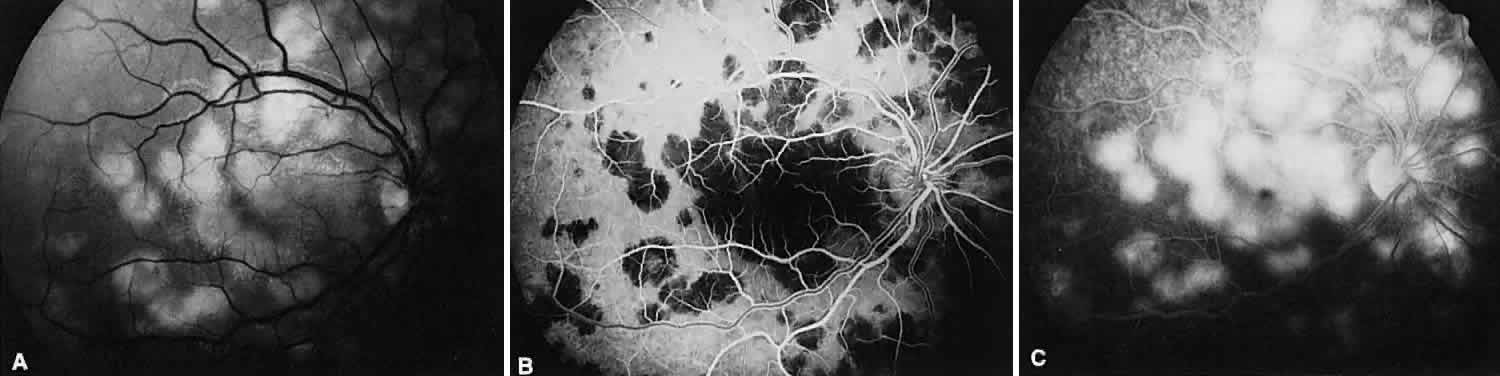

MULTIFOCAL CHOROIDITIS

Multifocal choroiditis may mimic the typical clinical findings of presumed ocular histoplasmosis syndrome (discussed later) and has the additional finding of anterior chamber and vitreous cells. Multiple yellow or gray acute choroidal lesions measuring 50 to 350 μm, periphlebitis, and occasionally retinal neovascularization can be seen. Marked pigmentary disturbances may be seen in the chronic phase (Fig. 11A).

Fig. 11. Multifocal choroiditis. A. Fundus photograph showing pigmentary disturbances. B. Multiple areas of hypofluorescence and hyperfluorescence representing chorioretinal scars with associated atrophic areas. C. Indocyanine green angiogram shows multiple areas of hypofluorescence around the disc, the macula, and the midperipheral fundus. Some of these areas are not visible clinically or on fluorescein angiogram.

On fluorescein angiography (see Fig. 11B), the punched-out lesions show the typical window defects. Acute lesions block early choroidal fluorescence and stain late. Cystoid macular edema and prolonged arteriovenous circulation times may be seen.39 Progressive subretinal fibrosis is a reported sequela that presents as multiple stellar zones of subretinal fibrosis. This fibrosis can be surrounded by multiple atrophic punched-out lesions (Fig. 12).40

Fig. 12. Multifocal choroiditis with subretinal fibrosis in a 26-year-old woman. A and B. Color photographs show hypopigmented lesions representing subretinal fibrosis involving both macular lesions. Multiple punched-out lesions surround the bands of fibrosis. C. Staining of the large stellate fibrous lesion can be seen in the left macula. There are multiple punched-out lesions above and below the macular zone. Leakage from the optic disc and its vessels can also be seen.

ICG angiography shows large hypofluorescent spots in the posterior pole measuring 200 to 500 μm, which did not usually correspond to clinically or fluorescein angiographically detectable lesions (see Fig. 11C). Smaller hypofluorescent spots, less than 50 μm, also may be seen in the posterior pole. Both large and small lesions are best seen in the later phases of the angiogram. Confluent hypofluorescent areas may be seen around the optic nerve in patients reporting an enlarged blind spot on visual field testing.41